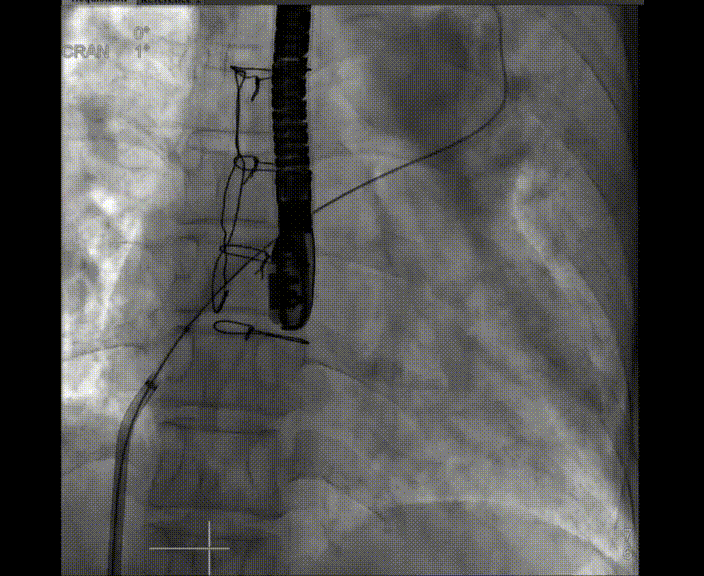

術(shù)中首先在局麻下穿刺股動(dòng)脈、股靜脈,完成心導(dǎo)管檢查評(píng)估后轉(zhuǎn)為全麻,在食道超聲引導(dǎo)下穿刺房間隔,穿刺成功后將加硬導(dǎo)絲送入左上肺靜脈建立軌道,根據(jù)患者病情行球囊預(yù)擴(kuò)張后植入6mm孔徑房間隔造孔支架,經(jīng)透視及食道超聲評(píng)估支架左右盤展開良好,夾持于房間隔兩側(cè),固定穩(wěn)定、位置良好,食道彩超顯示房水平右向左為主分流,分流孔直徑符合預(yù)期大小,心導(dǎo)管檢查評(píng)估達(dá)到預(yù)期效果,釋放造孔支架。術(shù)后12h患者下床活動(dòng),恢復(fù)順利,擬于近日完善術(shù)后評(píng)估后出院。